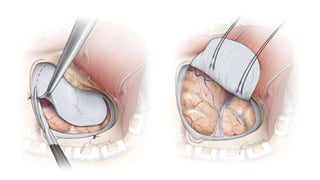

• SPECIFIC MANAGEMENT

• Clipping

• Pterional approach

• Bifrontal approach

• Coilling

MANAGEMENT • SPECIFIC MANAGEMENT •Clipping • Pterional approach • Bifrontal approach • Coilling